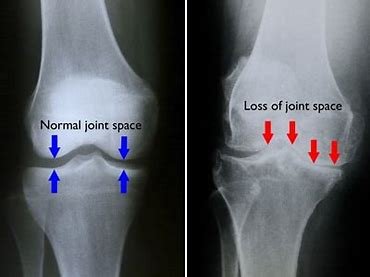

Biomechanics of Knee Osteoarthritis

Knee osteoarthritis (OA) is not only cartilage degeneration; it is strongly influenced by faulty biomechanics, abnormal loading, muscle imbalance, and poor lower-limb alignment.During walking, standing, and stair climbing, the knee bears high loads. When alignment is disturbed, excessive stress falls on one compartment—most commonly the medial compartment—leading to cartilage wear,...